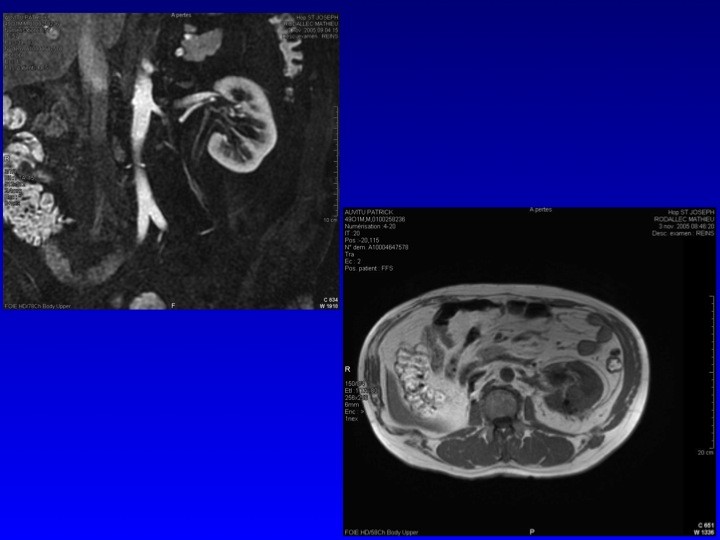

Prise en charge des petites tumeurs rénales en 2011 : diaporama 3